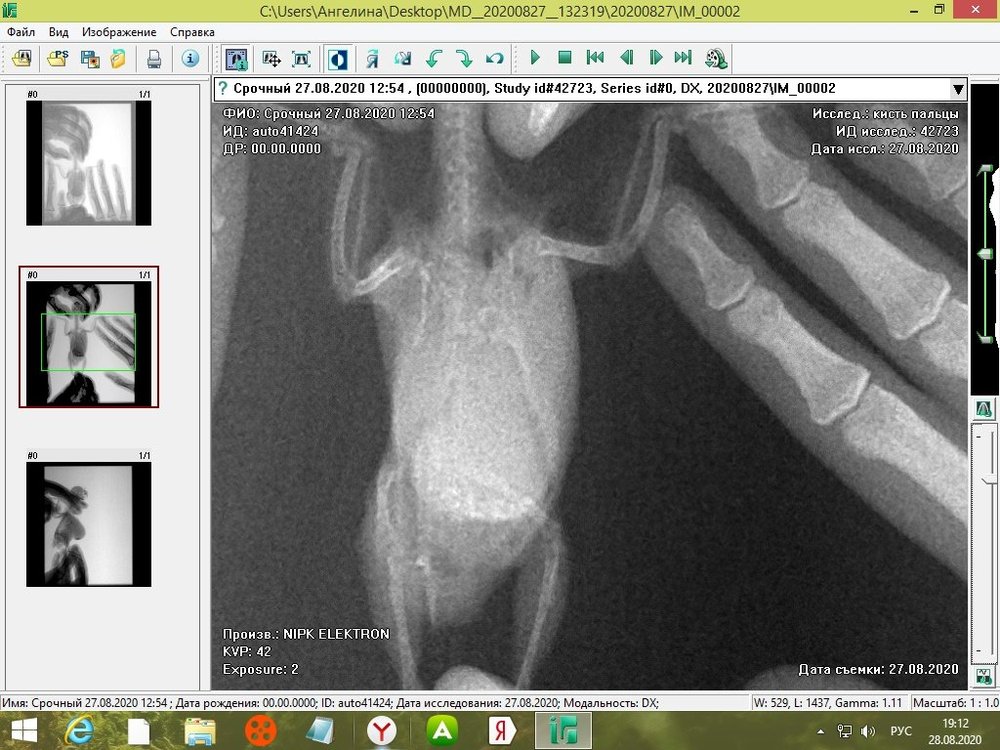

tanushka-sol2020 Опубликовано 27 августа, 2020 Автор #15 Опубликовано 27 августа, 2020 Некадрированные исходные снимки --- щёлкните полосу ниже. Скрытый текст

Кузяныч Опубликовано 28 августа, 2020 #16 Опубликовано 28 августа, 2020 Ох, бедная волнушка... В помёте на шли бактерии (++), слизь (+), жир (+), клетчатку (++)... Есть и непонятные для меня записи... По рентгену на втором снимке справа мне видится что эта огромная припухлость --- растянутый зоб... 18.08.2020 в 17:16, tanushka-sol2020 сказал: Что за опухоль? Она в моих руках меняется: то сморщится, то раздувается как шар надувной... Неужели, действительно зоб?... @tanushka-sol2020, срочно звоните Зосе, просите посмотреть снимки. Мазок из клюва... уф-ф... не знаю пока на сколько он нужен... Если на нистатине птице легче, то давайте его --- придерживайтесь дозировок, что давала вам Зося. Расположите лесенку горизонтально чтоб попугайчик экономил силы. Установите всё как можно ниже к полу. Проверьте, чтоб птичка не пыталась лезть выше и не висла на стенке. Помёт оранжевый... возможно, действительно, печень страдает... Карсил не отменяйте... За гепатовет и как вообще быть я не могу сказать. Нужно чтоб Зося посмотрела рентген. Свяжитесь, пожалуйста, с ней. У меня такое впечатление, что у этой волнушки растянут зоб и от этого плохо уходит и застаивается, протухая, пища.

tanushka-sol2020 Опубликовано 28 августа, 2020 Автор #17 Опубликовано 28 августа, 2020 (изменено) @Кузяныч К сожалению, от нистатина у нее сильно страдает печень. Я не стала ей давать, почти 3 недели принимали. Но срыгивание снова вернулось. Когда я собирала мазок из глотки, она потом срыгнула на одежду. Капли были песочного цвета и консистенция, как каша жиденькая. Но с запахом. Переживаю, вдруг неправильно сделала мазок, впервые же. Во вторнике будет готов анализ. Отпишусь. Рентген делали в больнице, я их кое-как уговорила. Первый "блин с комом", тоже выложила. Вдруг качества нет на снимке, что показал. Завтра Зосе позвоню. Спасибо, что ответили. Эти снимки неудачные выше, племянница скидывала. Я немного контраст отрегулировала, чтобы было видно. Изменено 28 августа, 2020 пользователем tanushka-sol2020

Zosia Опубликовано 30 августа, 2020 #23 Опубликовано 30 августа, 2020 Автор, вы самодеятельно изменили дозировку нистатина птице. Тем амым вы вырастили резистентную к нистатину грибковую флору. Так что теперь вам придется покупать Амфотерицин В. И Гептрал.скорее всего. Как купите- напишите что и в какой дозе купили. Далее. наконец перо на груди и зобу птицы, отчешите его- и сфотографируйте тот кошмар,который под пером прячется. По форме это- не липома.Точнее так- сейчас не липома. Далее. Прощупайте "мешок" зоба тщательно, натощак, пытаясь ощутить- есть ли между противопоставленными стенками зоба "лишнеяя" ткань. Если есть- то какая- плотная, дольчатая.цельная, четко отграниченная или нет. На дней того,что находится на месте зоба- я вижу конкременты. Не давать птице никаких камушков и песка! Учитывая вес объекта и вес птицы- она на самом деле весит едва 30 граммов. Обогрев- круглосуточный. Корма- самые любимые. По уму- зоб вскрывать и смотреть что внутри. Прогноз- отрицательный..